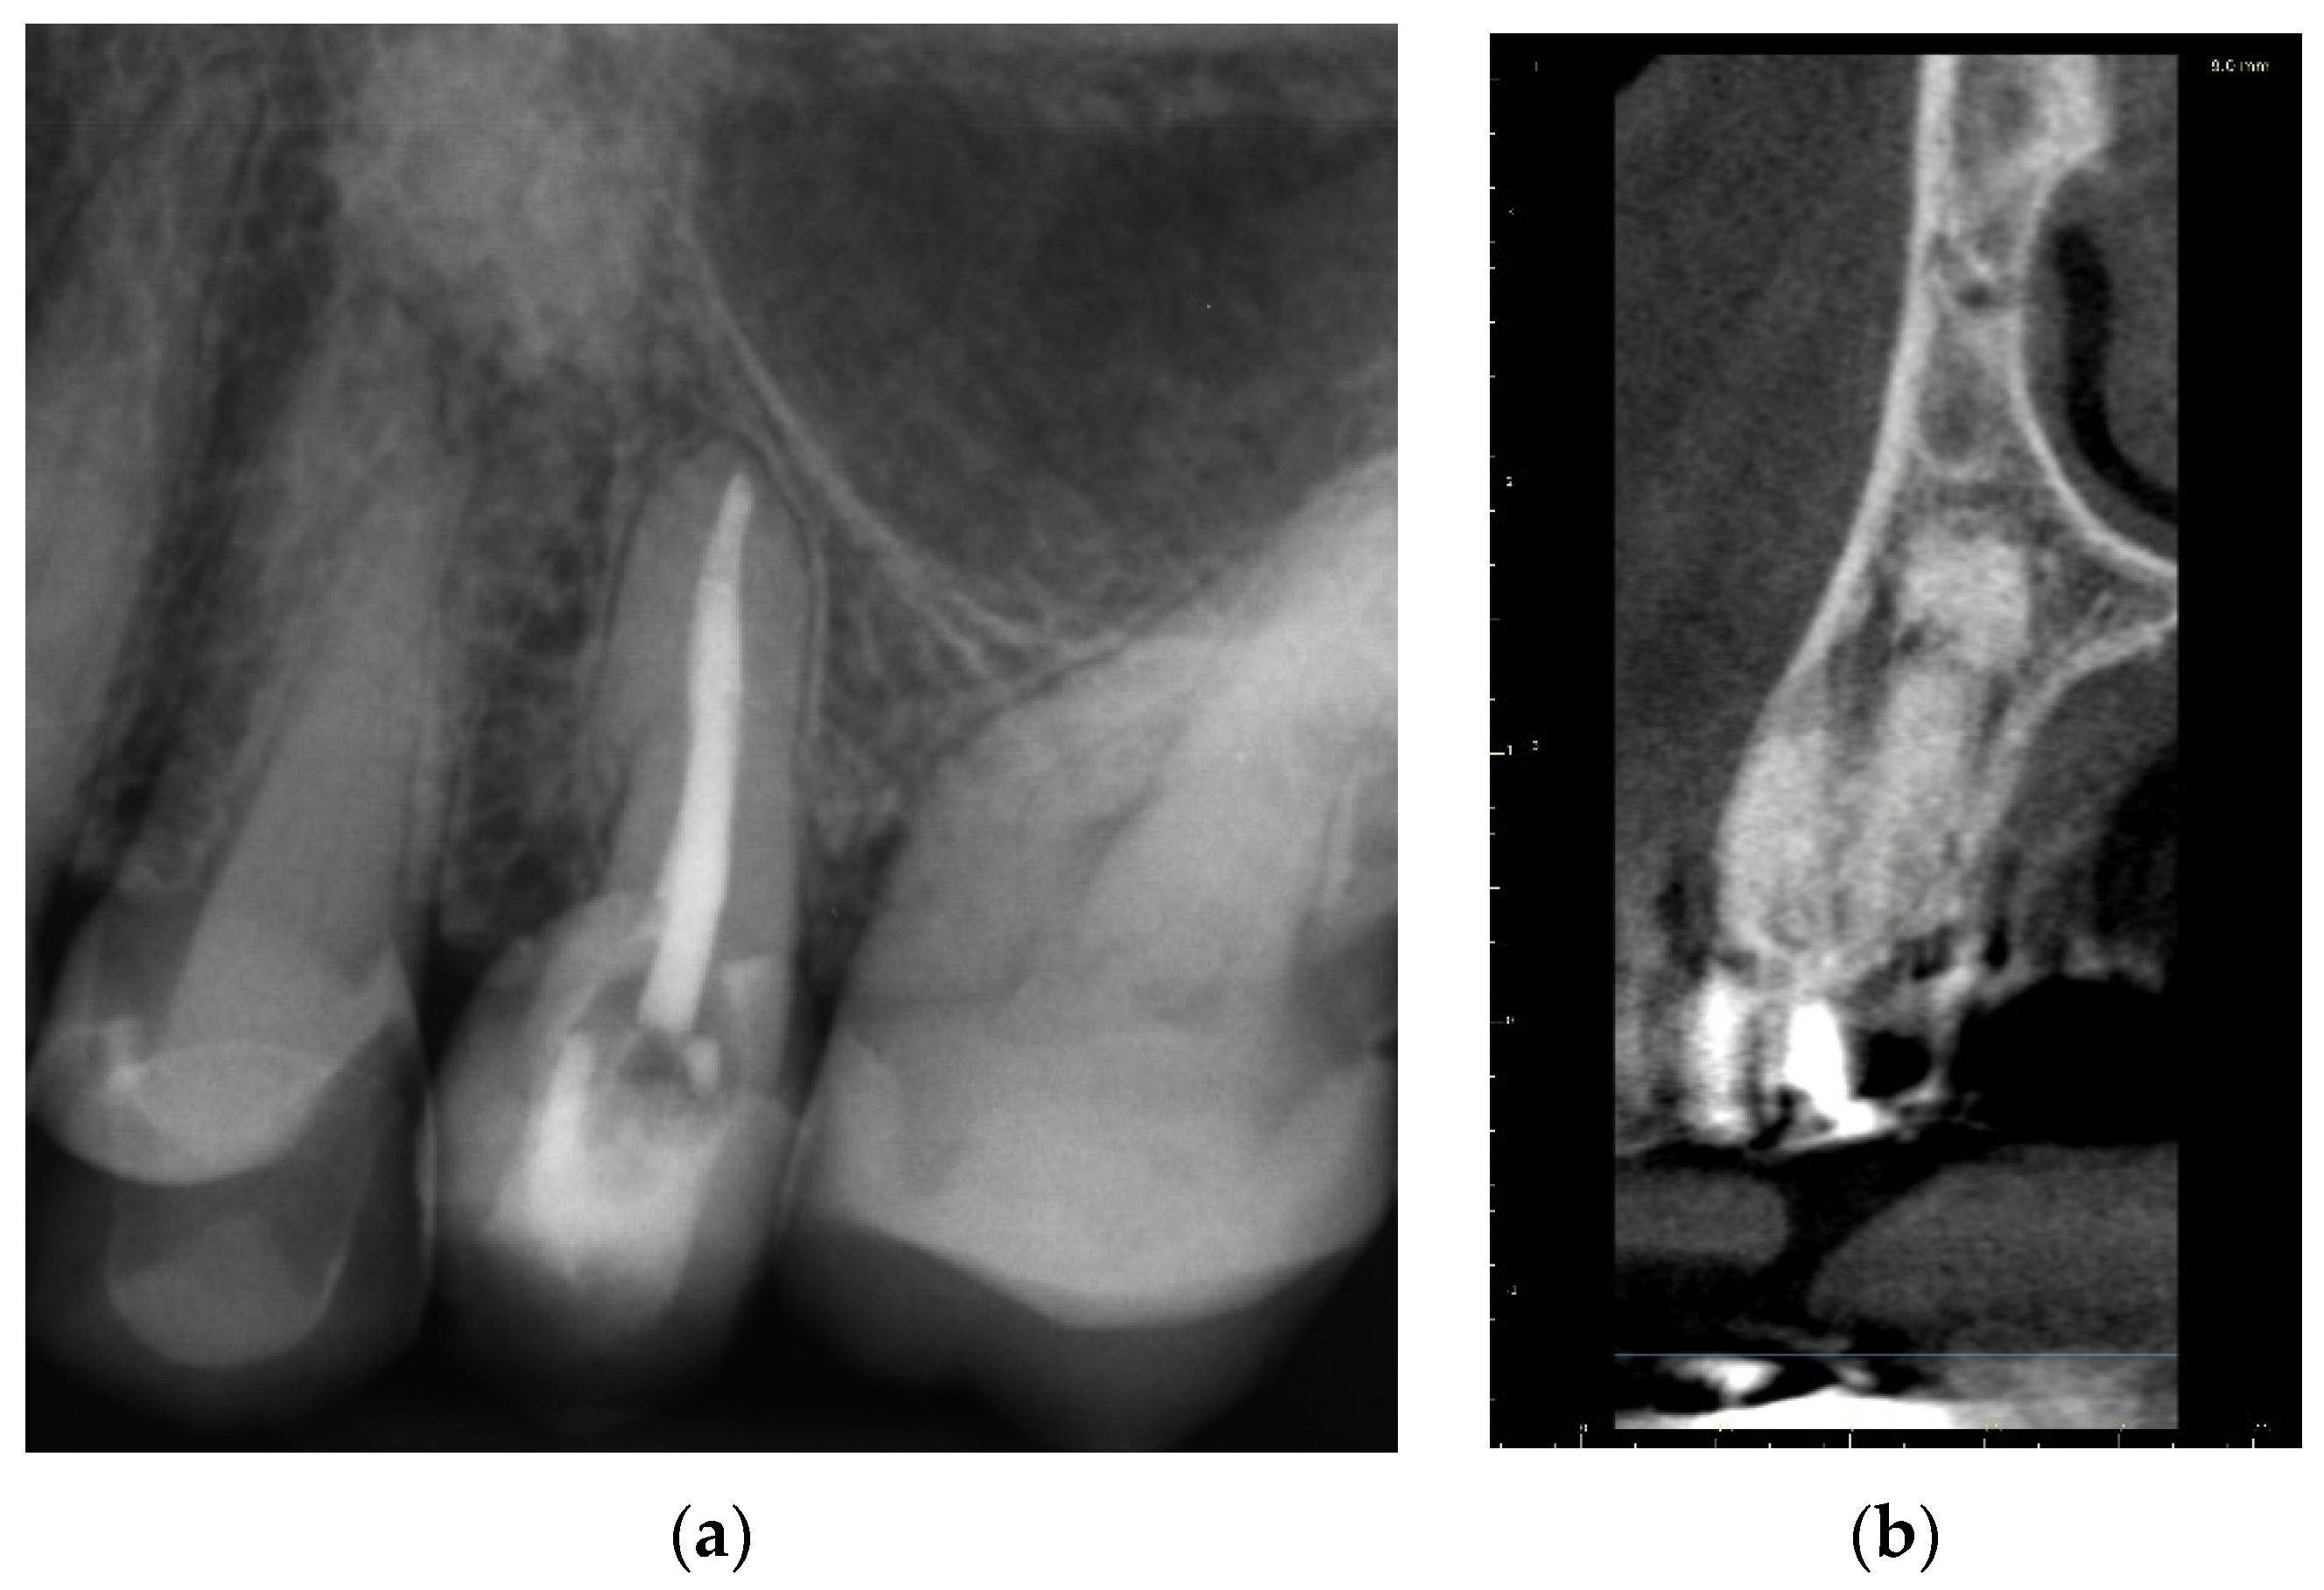

A 39-year-old male patient was referred to an endodontic specialist for the treatment of a maxillary left central incisor (tooth 21) before prosthetic treatment. Endodontic treatment had been initiated by the referring dentist, but as it was impossible for the clinicians to localize the root canal under the optical microscope, the treatment could not be completed, and the patient was referred to a specialist. The patient’s medical history revealed the absence of any systemic disorders or allergies. The dental history revealed trauma to the maxillary anterior region in childhood and subsequent gradual discolouration of the maxillary left central incisor. The patient presented with no complaints. Clinically, there were no pain or sensitivity to percussion or palpation. Tooth mobility was not increased. The tooth was restored by the referring dentist with a temporary restoration (composite resin) and showed no response to the pulp sensibility test (cold test). The radiograph and CBCT images showed that the endodontic treatment was initiated with wide access in the coronal part and confirmed root canal obliteration (Figure 16). After discussing the high probability of perforation and further tooth substance loss, an endodontic guide was designed.

Figure 16. The failed wide access in the coronal part and root canal obliteration on (a) X-ray and (b) CBCT images.